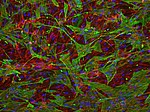

My group is interested in the regulation of cerebral blood flow at the blood brain barrier (BBB) and in the distinct roles of the involved cells types. The BBB is formed by vessels and consists of the basement membrane and cells, which have special properties leading to a very tight and highly organized structure at the interface between blood and brain.

In a healthy brain, the BBB prevents neural tissue from the invasion of pathogens, the infiltration of immune cells and extravasation of serum proteins. In addition, brain cells have a high demand for glucose, oxygen, and other factors, coming from the blood. The perfusion with blood is tightly regulated in terms of time and localization. In this process different cell types, including neurons, astrocytes, pericytes, smooth muscle cells, and endothelial cells, are activated and all of them are able to influence the kinetics and amplitude of perfusion. If the communication between these cells is dysregulated as in stroke, dementia, diabetes, or obesity, also vascular reactivity is altered.

We are interested in intercellular connections, especially in those that involve endothelial cells, and in the effects of endothelial dysfunction on related brain functions. For this purpose we are using state-of-the-art technologies like two-photon microscopy, tissue-specific knockout animal models, and virus-mediated gene transfer.